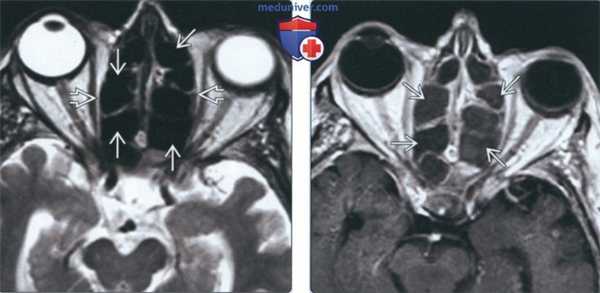

(Слева) На рисунке в корональной плоскости показаны классические признаки аллергического грибкового синусита (АГС), включая снижение пневматизации и вздутие нескольких придаточных пазух и полости носа. В центре виден плотный материал, окруженный по периферии отечной слизистой оболочкой.

(Справа) При аксиальной КТ без КУ определяется односторонний аллергический грибковый синусит. Пораженные пазухи вздуты и содержат плотный «выветренный» материал в центре, окруженный гиподенсным ободком по периферии. Поражение пазух при АГС может быть одно- или двухсторонним.

(Слева) При аксиальной МРТ Т2ВИ у пациента с двухсторонним АГС определяется диффузный гипоинтенсивный сигнал в пораженных ячейках решетчатой кости. Определяется легкое вздутие пазухи с латеральным смещением глазничной пластинки. Обратите внимание на очень низкую интенсивность сигнала, что создает впечатление о нормальной воздушности пазухи.

(Справа) При аксиальной МРТ Т1ВИ С+ у этого же пациента определяется тотальное снижение пневматизации ячеек решетчатой кости. Слизистая оболочка накапливает контраст по периферии.

(Слева) На аксиальной МРТ (Т2 ВИ) у пациента с двухсторонним АГС определяется диффузный гипоинтенсивный сигнал в пораженных ячейках решетчатого лабиринта. Ячейки слегка вздуты, глазничные пластинки Я дугообразно выбухают кнаружи. Обратите внимание на сигнал крайне низкой интенсивности, имитирующий нормальную пневматизацию пазухи.

(Справа) На аксиальной MPT (Т1 ВИ С+) у этого же пациента определяется тотальное снижение пневматизации ячеек решетчатого лабиринта. Слизистая оболочка накапливает контраст.